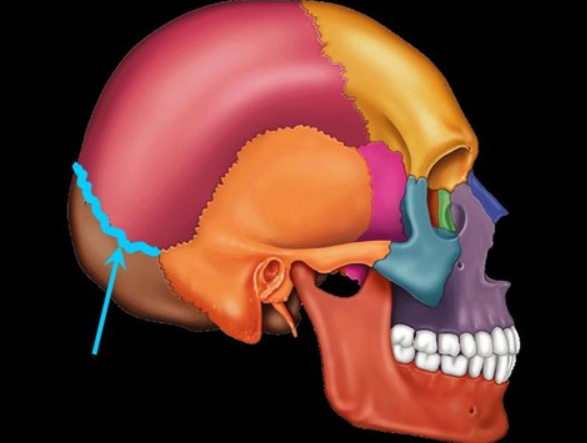

lamboid suture

sits between the occipital and parietal lobe